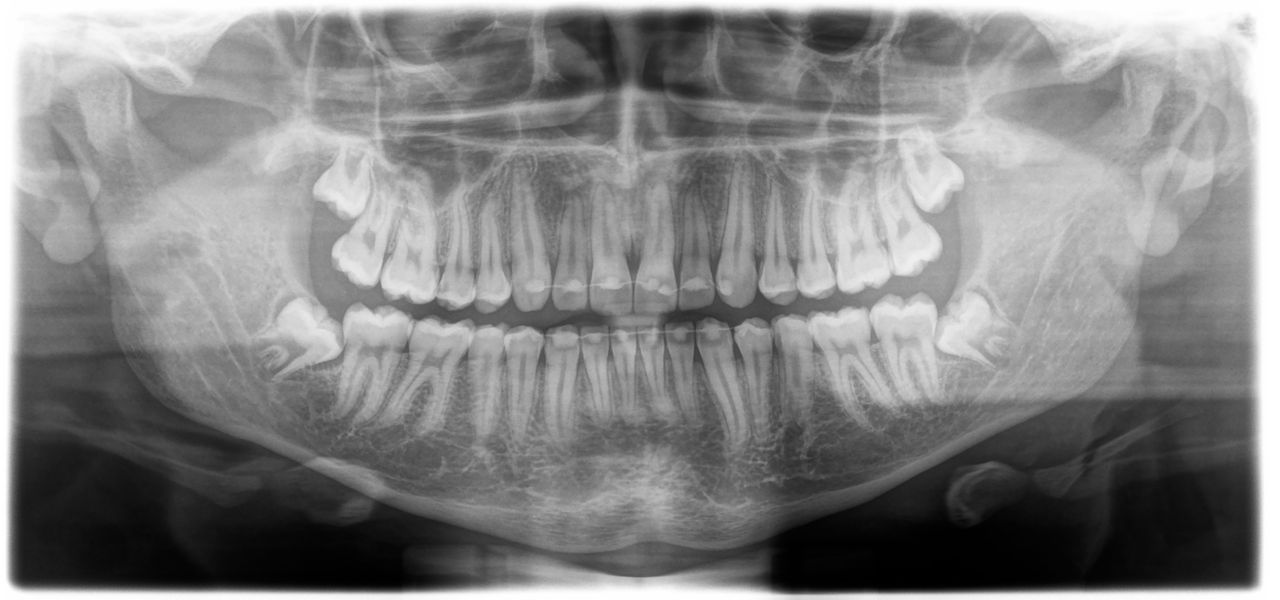

La collecte de données radiographiques panoramiques est essentielle pour un diagnostic optimal et la planification du traitement, ainsi que pour le séquençage de la thérapie. Le cours examine les bases de l’évaluation systématique des images panoramiques. Il couvre également les repères anatomiques ordinaires ainsi que les anomalies courantes observées sur les radiographies panoramiques.